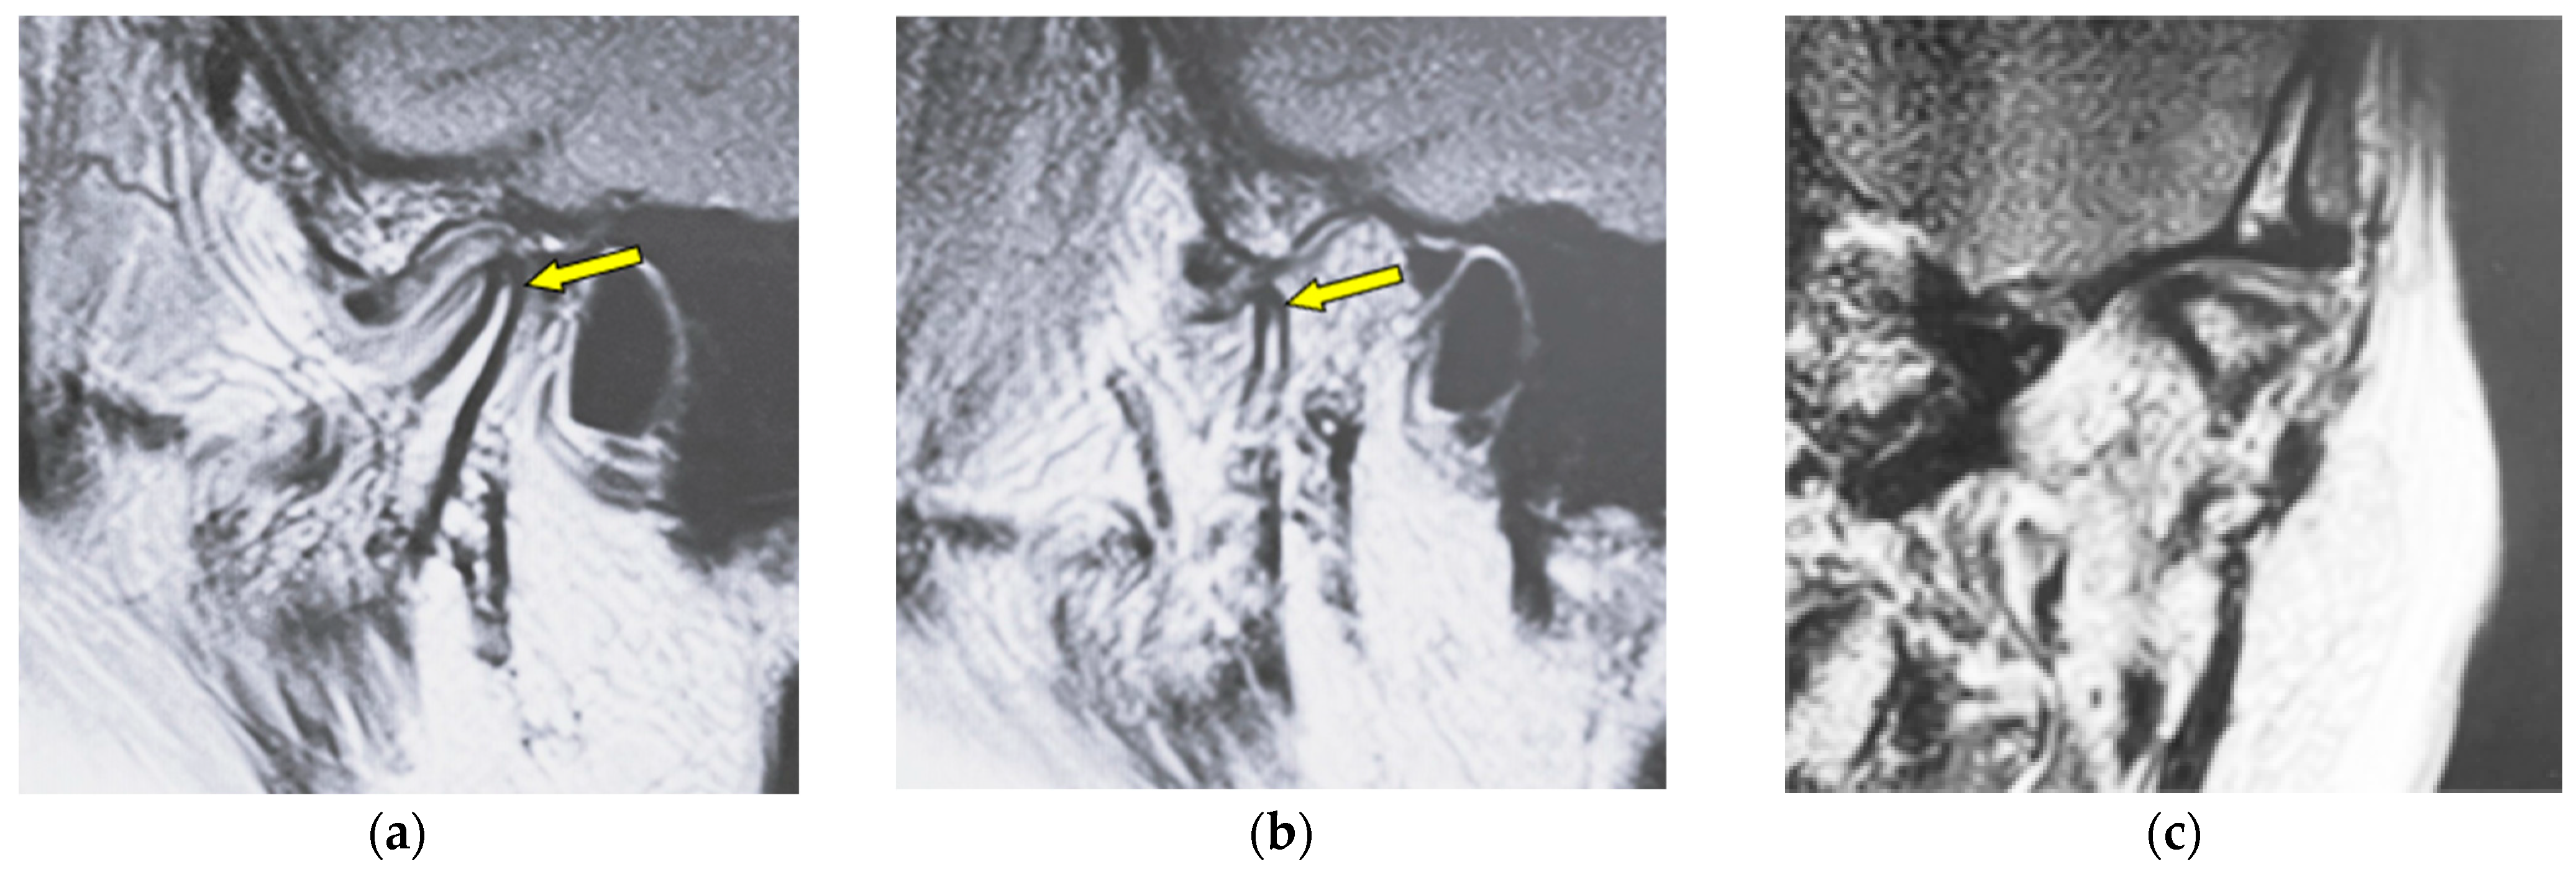

Figure 4 shows MR images of an 82-year-old woman with atrophy (left TMJ). Sagittal oblique cross-section imaging (proton-density-weighted) shows anterior disc displacement in the mouth-closing position (Figure 4a) and in the mouth-opening position (Figure 4b).

MR image (proton-density-weighted) of an 82-year-old woman (disc displacement without reduction, left disc): (a) sagittal oblique cross-section imaging in the mouth-closing position; (b) sagittal oblique cross-section imaging in the mouth-opening position; (c) coronal oblique cross-section imaging in the mouth-closing position. The arrow shows the part with atrophy.